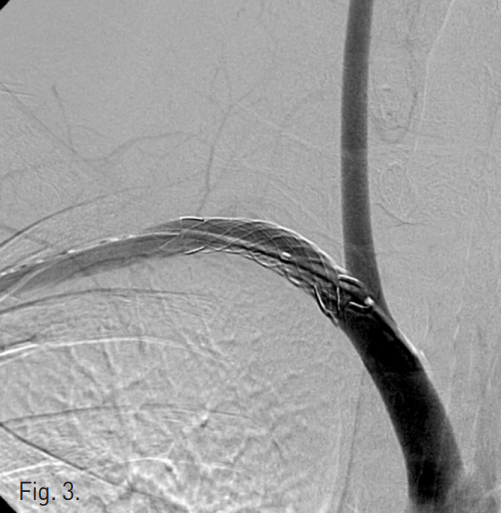

초음파 유도하에 우측 액와동맥(axillary artery)을 천자하여 8F sheath(Terumo, Tokyo, Japan)를 삽입하였다. 5F angiographic catheter(Terumo)와 0.035" guidewire(Terumo)로 우측 쇄골하동맥을 선택하였다. Angiographic catheter를 fistula의 원위부로 진입하고 0.035" stiff guidewire(Terumo)로 교체하였다. 쇄골하동맥의 fistula 부위에 10mm × 4cm PTFE-covered stent graft(Seal; S&G, Seoul, Korea)를 삽입하였고 10mm × 2cm balloon catheter(Ultra Thin; Boston Scientific, Galway, Ireland)로 확장하였다. 우측 무명동맥조영술에서 stent graft를 통한 혈류는 잘 유지되어 있으며 동정맥루는 더 이상 보이지 않았다(Fig. 3). 시술 후 환자는 특이소견 없었으며 이학적 검사에서 떨림이 소실되었다.

Fig. 3

After successful stent graft placement at right subclavian artery, there was no residual blood flow through the arteriovenous fistula.